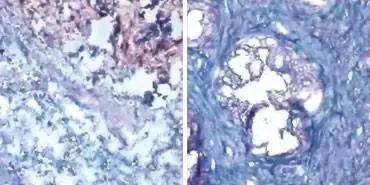

癌组织具有额外的糖(染色蓝色),其与天然*伤杀**细胞上的蛋白Siglec-9结合,并且使免疫反应停止。 左图显示乳腺癌组织; 右显示前列腺癌。